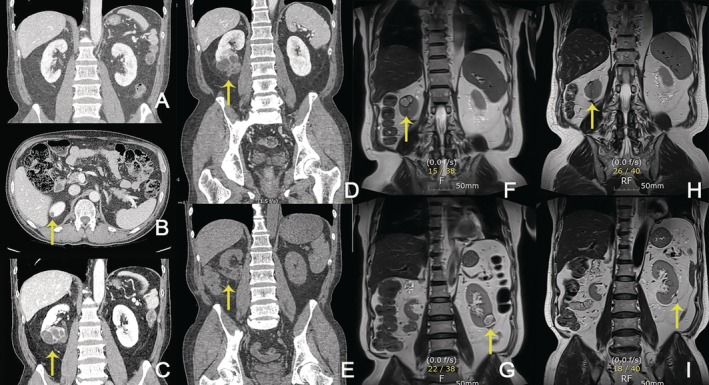

Crizotinib, an anaplastic lymphoma kinase (ALK)/ROS1/c-MET inhibitor, improves outcomes in ALK-positive non-small cell lung cancer (NSCLC) but can cause crizotinib-associated renal cysts (CARCs), a rare yet clinically relevant adverse effect. We report a case of a 68-year-old Korean male who developed complex renal cysts after 4 years of crizotinib therapy. Radiologic findings initially raised suspicion for either an abscess or a neoplastic lesion, leading to surgical resection. However, recurrent renal cysts developed during continued crizotinib therapy, and CARCs were subsequently suspected. A dose reduction was implemented, which led to cyst regression without compromising tumor control. This case highlights the need to recognize and manage late-onset toxicities during long-term treatment, emphasizing the clinical value of multidisciplinary evaluation and tailored dose adjustments.

克唑替尼是一种间变性淋巴瘤激酶(ALK)/ROS1/c-MET抑制剂,可改善ALK阳性非小细胞肺癌(NSCLC)的预后,但可引起克唑替尼相关肾囊肿(CARCs),这是一种罕见但临床相关的不良反应。我们报告一例68岁的韩国男性谁发展复杂的肾囊肿后4年的克唑替尼治疗。放射学结果最初怀疑为脓肿或肿瘤病变,导致手术切除。然而,在继续克唑替尼治疗期间,复发性肾囊肿出现,随后怀疑为CARCs。减少剂量,导致囊肿消退而不影响肿瘤控制。该病例强调了在长期治疗过程中识别和管理迟发性毒性的必要性,强调了多学科评估和量身定制剂量调整的临床价值。